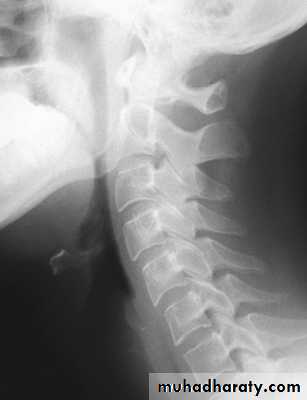

Cervical Spine X-RayLateral radiograph

A/P radiographThoracic Anatomy

Cervical Spine AnatomyNormal curvature is lordosis

Spinous Processes are BifidA flexible group of vertebrae that support the skull